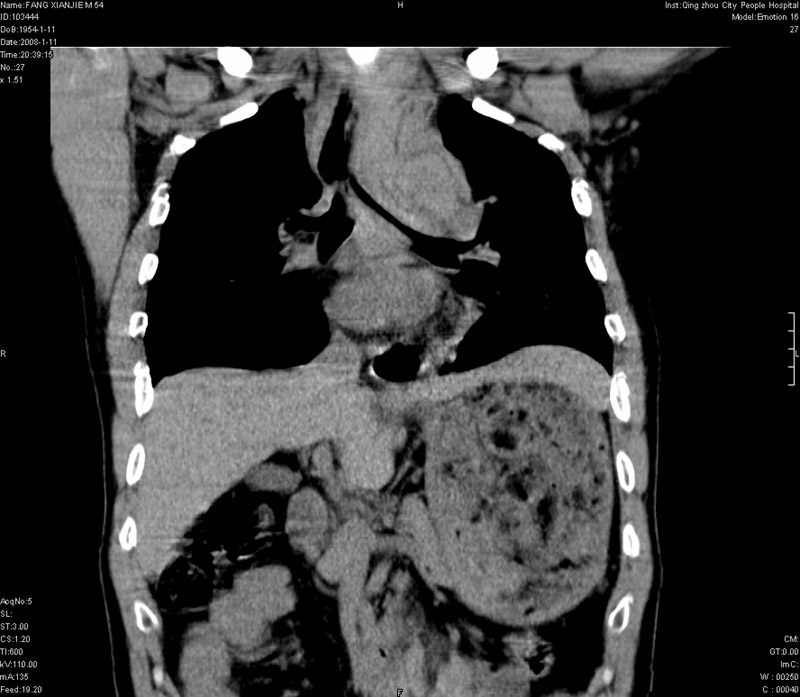

男性,40岁。胸部被车压伤伴胸痛1小时来院就诊。检查:一般情况尚可,血压110/80,胸部及上腹部压痛。结果在三天后公布。骨窗在横断位、冠矢状显示肋骨、胸椎、和胸骨未见骨折征象。

ct11308:胸部外伤1小时(证实病例) (2008-1-13 16:2)结果如下:病人入院后两小时后症状加重,8小时后在征得病人家属同意做了ct增强扫描。如下图。最终临床诊断:外伤性胸主动脉破裂并纵隔内血肿。由于有运动性伪影,胸骨在矢状面重建的图像似有骨折征,这是一种假象,我们称之为“假骨折”,这在多层ct重建中经常性遇到,必要时要结合横断图像鉴别之。现在,病人的一般情况较差,是否要手术家属尚有争议,如果手术修补,难度较大,需要专门预定制作固定支架。

以下是引用拾荒者在2008-1-16 18:46:00的发言:[br]ct11308:胸部外伤1小时(证实病例) (2008-1-13 16:2)结果如下:病人入院后两小时后症状加重,8小时后在征得病人家属同意做了ct增强扫描。如下图。最终临床诊断:外伤性胸主动脉破裂并纵隔内血肿。由于有运动性伪影,胸骨在矢状面重建的图像似有骨折征,这是一种假象,我们称之为“假骨折”,还有双侧肋骨的“假骨折”,这在多层ct重建中经常性遇到,必要时要结合横断图像鉴别之。现在,病人的一般情况较差,是否要手术家属尚有争议,如果手术修补,难度较大,需要专门预定制作固定支架。[br][br]再次表示感谢!

当然,对于该病例,其它非重要的诊断还有:右侧少量气胸;左侧胸腔积液;左侧轻度肺挫裂伤。对于纵隔内血肿,我们曾经遇到过多例,也有怀疑主动脉的破裂,但是,均未得到具体出血部位的明确诊断。